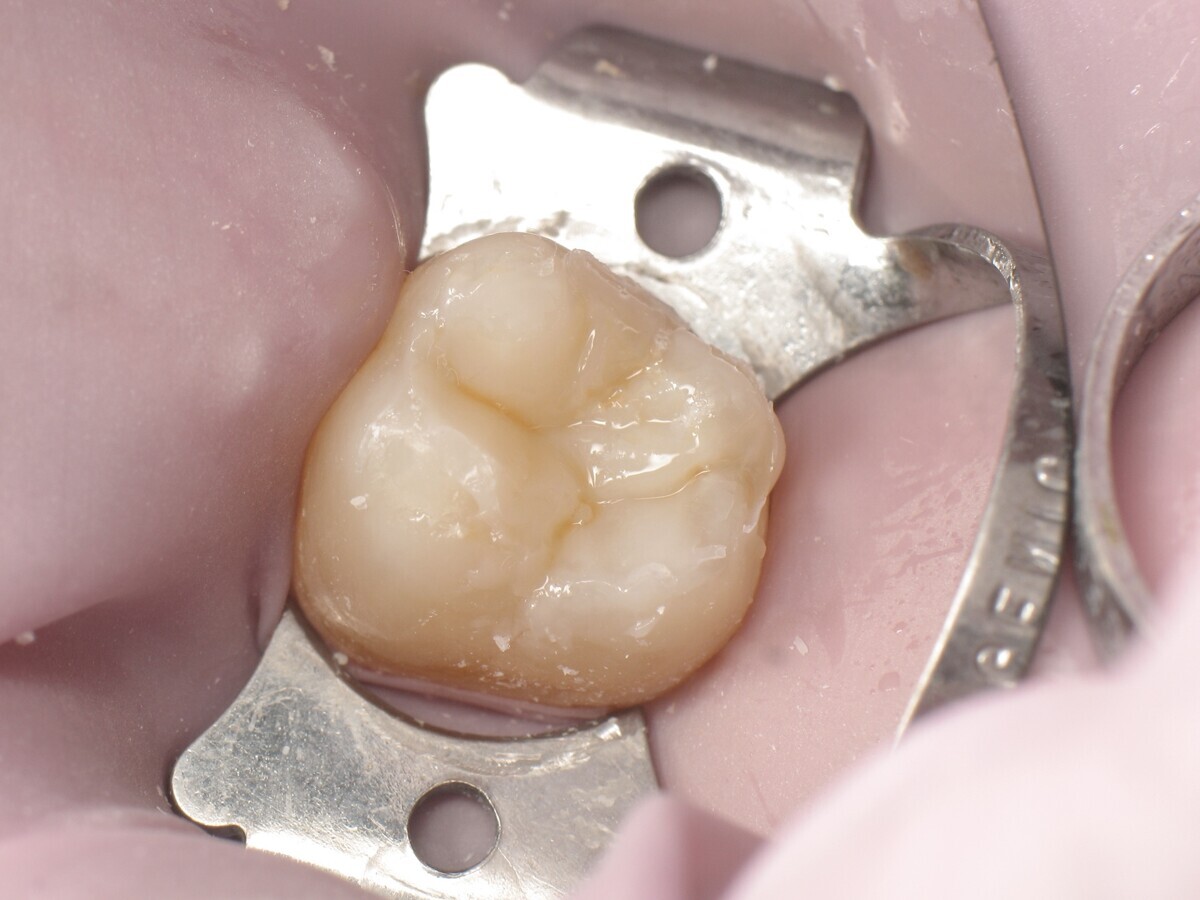

La secuencia fotográfica muestra la cavidad después de la aplicación y fotopolimerización del adhesivo y el modelado que se obtiene con el composite termoviscoso. Fotos: Yassine HARICHANE

Este artículo describe el tratamiento de una cavidad clase I en un molar utilizando un composite termoviscoso mediante la técnica de la almohadilla (Figura 1). En primer lugar, se registran los detalles anatómicos utilizando una resina transparente, fluida y fotopolimerizable (Clip Flow, VOCO). El diente se aísla con un dique antes de aplicar el composite transparente a la superficie oclusal con un cepillo aplicador y fotopolimerizar durante 10 segundos (Figuras 2-4). La almohadilla oclusal así obtenida (Figura 5) debe almacenarse en alcohol (etanol o isopropanol) para eliminar la capa de inhibición. Luego se limpia la cavidad clase I (Figuras 6 y 7). A continuación se graba el esmalte durante 30 segundos y la dentina durante 15 segundos (Conditioner 36, Dentsply Sirona) y luego se enjuaga bien (Figuras 8 a 10). Debido al bajo espesor de la dentina remanente, también se aplica protección pulpar (Telio Desensitizer, Ivoclar Vivadent) (Figura 11). Luego se frota el adhesivo sobre las superficies dentales durante 20 segundos (Futurabond DC, VOCO), luego se seca bajo una pulverización de aire sin aceite graso durante 5 segundos y luego se fotopolimeriza durante 10 segundos (Figuras 12, 13). Para una humectación óptima, el fondo de la cavidad se cubre con un compuesto fluido de baja viscosidad (GrandioSO Light Flow, A3.5, VOCO) y se fotopolimeriza durante 20 segundos (Figuras 14, 15). Utilizando el Dispensador VisCalor, un dispensador portátil que permite el calentamiento y la aplicación simultánea de resinas, la cavidad se llena luego con un composite termoviscoso bulk (VisCalor Bulk, A2, VOCO).

El composite calentado tiene una consistencia fluida para un perfecto manejo y se puede aplicar en capas de hasta 4 mm (Figura 16). A medida que se enfría hasta la temperatura corporal, la viscosidad del composite termoviscoso aumenta, lo que lo hace muy fácil de modelar (Figura 17). Finalmente, se realiza la fotopolimerización durante 20 segundos (potencia ≥ 1.000 mW/cm2, Figura 18). El uso de un composite bulk permite un llenado rápido en un solo paso. Si se requiere una segunda capa, la capa superior también se puede realizar con composite termoviscoso estético universal VisCalor en color A1 (VisCalor, VOCO, Figura 19), que se fotopolimeriza en incrementos de 2 mm. La consistencia innovadora del composite termoviscoso permite una reproducción fácil de la anatomía y una eliminación fácil del exceso de material (Figura 20) [Ilie et al. 2014]. A continuación se aplica la almohadilla oclusal creada previamente (Figura 21). La fotopolimerización se realiza primero con la almohadilla y luego sin durante 20 segundos cada una (Figuras 22 a 24). No se requiere material separador entre el material compuesto y la almohadilla. Debido a la eliminación previa de la capa de inhibición de la almohadilla, hay muy pocos o ningún punto de contacto, de modo que no se puede crear ningún enlace químico real entre la almohadilla y la resina. Los pocos puntos de contacto presentes solo significan que puede sentir una ligera resistencia cuando se retira la almohadilla después del primer ciclo de fotopolimerización.